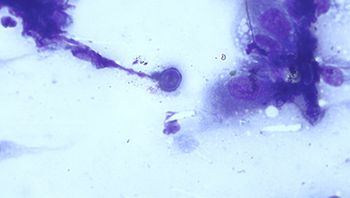

Below is a skin cytology from a 3-year-old male neutered Doberman pinscher with cutaneous lesions. Whats going on?

This skin impression cytology sample is from a 5-year-old, mixed-breed, spayed female dog.